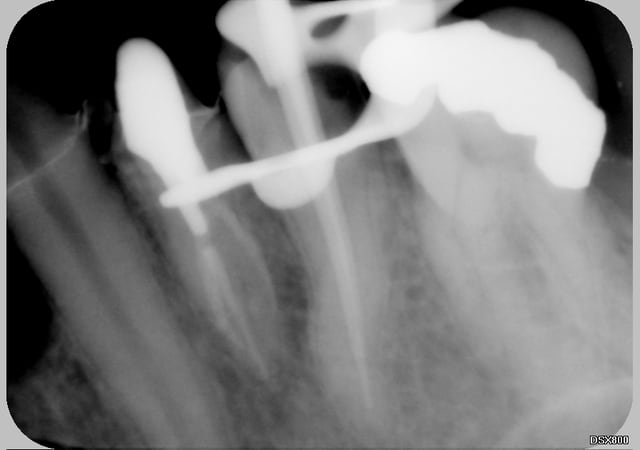

tient un boulot ou il y a un peu de tout.

bridge antérieur , car la pose d'implants nécessitait de la reconstruction trop importante, endo couronne sur les molaires mandibulaires par manque de hauteur, onlay. implants à la mandibule.

A noter les 2 PM maxillaires qui comportaient

chacune 3 canaux.